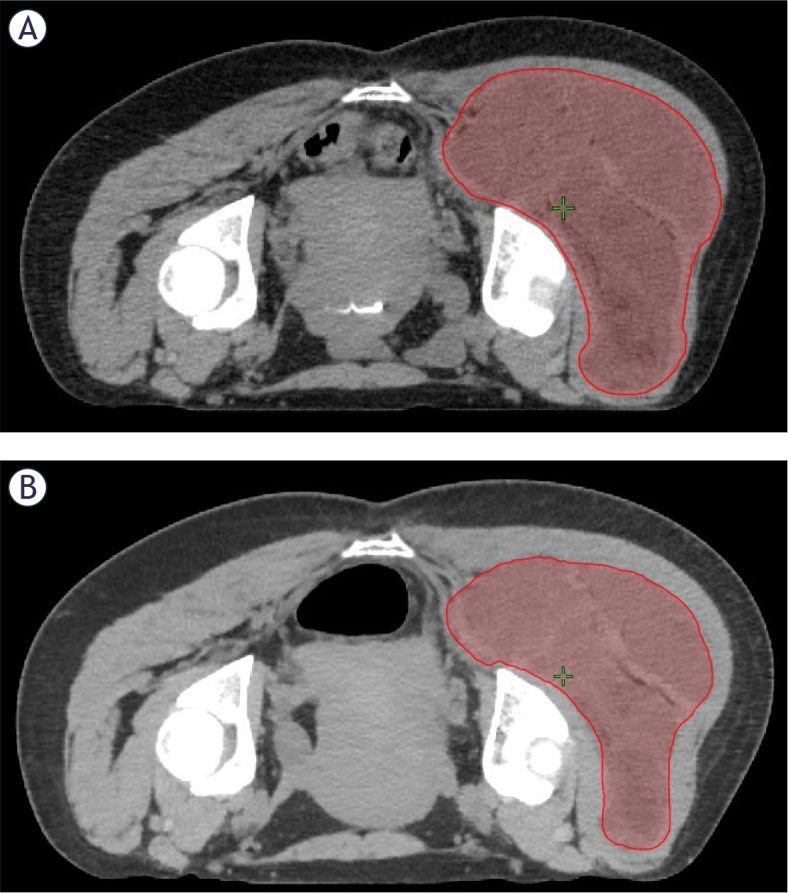

Patients and methods: We identified all patients with a histologic diagnosis of MLPS who received preoperative RT from 2013 to 2021 at our institution. We used cone beam computed tomography (CBCT) to assess changes in tumor volume and greatest dimension during treatment. Tumors were contoured on CBCT images prior to treatment and at the end of each week of RT. Percentage change in tumor volume and greatest dimension were calculated based on pre-treatment and final week contours. Patients with tumors incompletely visualized on CBCT were excluded from volume analysis but included on greatest dimension analysis. Magnetic resonance imaging (MRI) was used to evaluate pre- and post-RT radiographic features. Surgical pathology was reviewed to record pathologic characteristics.

Results: Twenty patients met inclusion criteria. Most tumors (18/20) were low grade. The most frequent dose/fractionation scheme was 50 Gy in 25 fractions (16/20), with 3 patients receiving 36 Gy in 18 fractions. Median pre-RT volume and greatest dimension were 120 cc (interquartile range [IQR]: 56-399) and 11.2 cm (IQR: 8.4-14.1), respectively. Median percentage change in volume and greatest dimension were -37% (IQR: -57 to -29) and -10% (IQR: -20 to -7). All evaluable tumors decreased in volume during RT. Between pre- and post-RT MRI, most patients had a decrease in intratumoral (16/20) and peritumoral edema (11/20). Sixteen patients exhibited extensive pathologic response. There were no significant associations between radiographic and pathologic features and volumetric change. Local failure at 3 years was 9% (95% confidence interval: 1-59).

Conclusions: We report significant decreases in MLPS tumor size during preoperative RT. There may be a role for adaptive RT planning to reduce target volumes and minimize RT-associated morbidity.